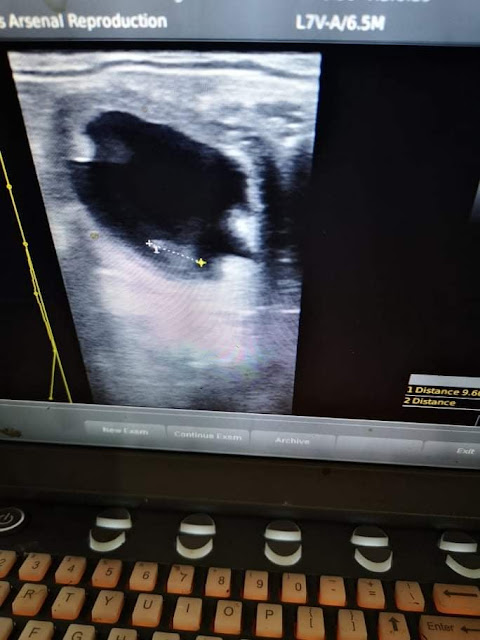

Luckily, my excitement was reignited the following day, when my scan showed a small vesicle! It measured more consistent with a 10-Day size, but alas - it was there! I decided to check back in 2 days for growth, and luckily it was still there and growing at an appropriate rate despite still measuring about 1 day smaller.

Sometimes, some embryo's just measure a little smaller, but as long as they're growing it's nothing worth worrying about but in Sierra's case, given that I know she double-ovulated, I think it's most likely she actually caught off the second ovulation instead of the first.

I checked Sierra a few more times since then; once to do a final twin-check before the vesicle implanted into the uterine lining, once more to check for growth, and then a final time to check for a heartbeat before making her pregnancy public knowledge.